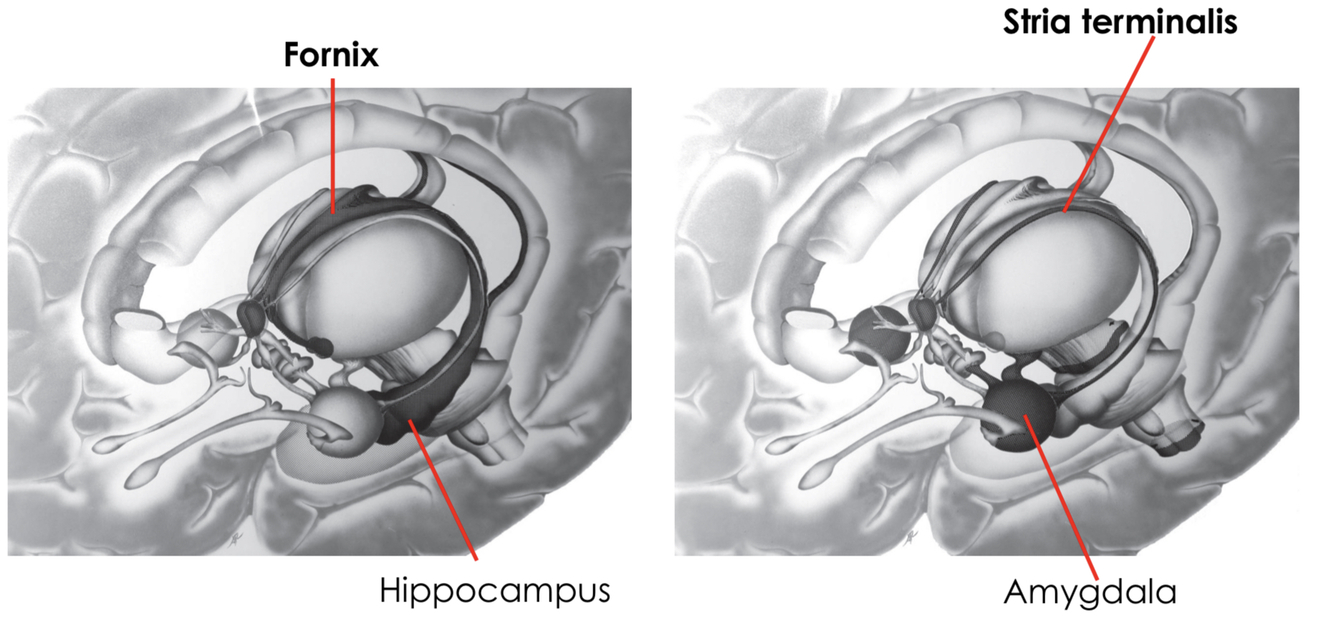

What are the connections associated with the limbic system?

Stria terminalis:

- connects the amygdala to the hypothalamus

Fornix:

- connects the hippocampus to the hypothalamus

- they both follow the curves of the lateral ventricles

What does the fornix connect to?

The fornix connects the hippocampus to the mammillary bodies of the hypothalamus

connecting to the hypothalamus immediately triggers functions of the hypothalamus, such as autonomic responses

emotions and memories can trigger autonomic responses e.g. increased heart rate

What is the outflow tract of the amygdala?

Stria terminalis

this is a band of fibres that runs along the ventricular surface of the thalamus (in lateral ventricle)